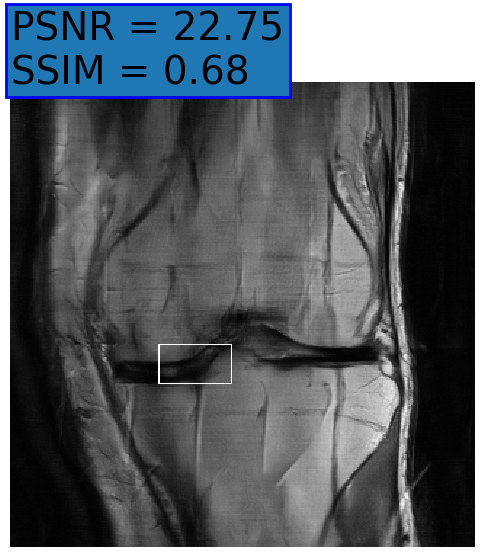

Figure 6: Examples of reconstruction results. Rows 1, 3, and 5: The reference (GT) fully sampled image, the reconstructed images obtained by the three models (1-3), NPB-REC, baseline, E2E-VarNet trained with Dropout, and the Std. map derived from our method for example from the knee dataset, the brain dataset, and the brain dataset sampled with radial mask L=50𝐿50L=50, respectively. Rows 2, 4, and 6: The corresponding annotated ROIs of the cartilage, edema, and nonspecific white matter lesion respectively.

Fig. 6 depicts the reconstruction results obtained by (1) our NPB-REC approach, (2) the baseline, and (3) Monte Carlo Dropout, for examples of both the knee (row 1) and the brain (rows 3 and 5) datasets. The first two examples were obtained by the models that trained on brain data and were tested on knee data (row 1) and vice versa (row 3). In knee images, all three models exhibit minimal differences in handling pronounced folding artifacts. However, our approach demonstrates superior reconstruction performance for anatomical annotations or pathological regions, labeled by radiologists, in terms of both PSNR and SSIM. The last example is a reconstructed brain image that was obtained by the three models, where the k-space input is undersampled by a radial mask with L=50𝐿50L=50. Table 2 presents the mean PSNR and SSIM metrics, calculated over the whole inference knee dataset, for the three models that were trained on brain data. The NPB-REC method shows a considerable improvement in the generalization ability on knee data for higher acceleration rates R=8𝑅8R=8 and R=12𝑅12R=12 in both annotation regions and the whole images. However, both the baseline and Dropout methods show a slight improvement in the metrics in the case of a small acceleration rate R=4𝑅4R=4. Table 3 shows the results of the inverse experiment, i.e. calculating the mean PSNR and SSIM metrics over the whole brain inference set for the three models that were trained on knee data only. The generalization capability of the three models in the case of an anatomical distribution shift from the knee to the brain is better than the opposite scenario. This is not only measured quantitatively by the SSIM and PSNR metrics, but also visible in the predicted reconstructions. For instance, the brain MRI reconstructed images exhibit fewer artifacts than the produced knee images, as shown in row 1 vs. row 3 in Fig. 6.

Table 3 presents the mean PSNR and SSIM metrics calculated over the whole inference knee dataset that were obtained by the three models, where the k-space input is undersampled by a radial mask with L=50𝐿50L=50 and L=40𝐿40L=40. Although the NPB-REC approach improves the accuracy of reconstruction when the metrics are measured on the whole image, it doesn’t yield the best performance on the annotation ROIs. However, it is still able to reconstruct high-quality images while preserving the important anatomical content in these annotations. This can be clearly observed in the last row in Fig. 6, where the topmost part of the ROI image predicted by NPB-REC is preserved, in contrast to the other benchmarks.